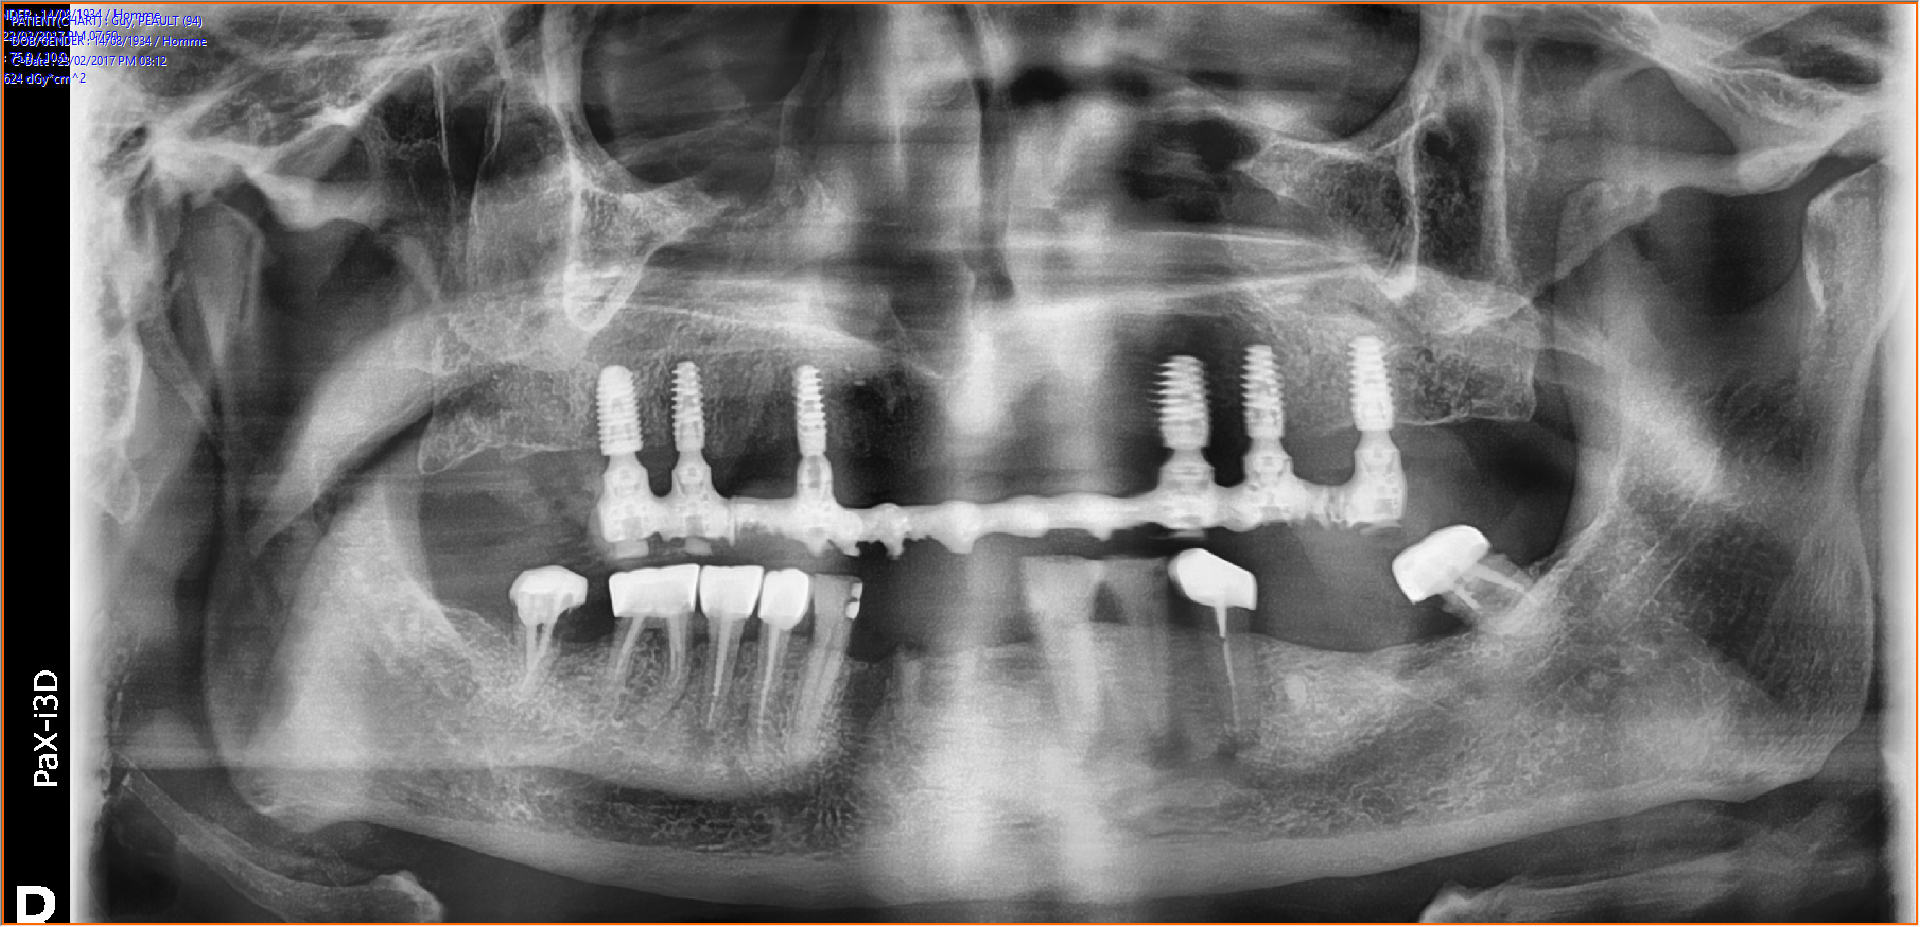

J'ai fait une simulation des implants avec CBCT. J'ai prévu utiliser Anthogyr axiom PX: 10mm de long, 4,6mm en postérieur et les 4 autres en 4mm.

Lors de la pose, l'assistante s'est trompé d'implant (et avec le stress je ne l'ai pas vérifié) pour le 24 (4,6 au lieu de 4mm). Je m'en suis rendu compte au moment de la 16 (plus de 4,6 en PX..) j'ai mis un 4,6 mais en REG, avec un blocage à 25N.

Ensuite la pose des piliers MU, droit standards sauf pour la 13 où j'ai du en poser à 20 degrés angulé pour suivre la crête antérieure bien résorbée.